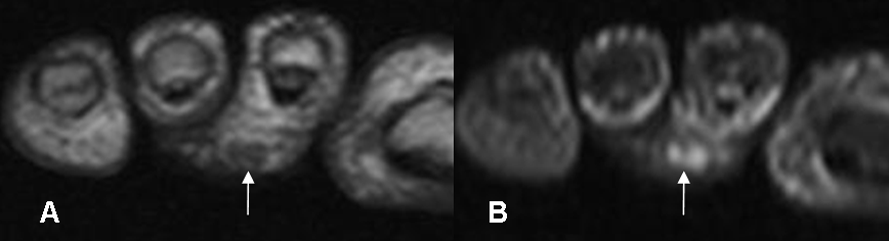

Fig 62. Pie diabético. Absceso.

A: RM coronal en T1 y B: RM coronal en STIR. Cambios inflamatorios en la parte posterior del 2º metatarsiano, con formación de pequeño absceso.